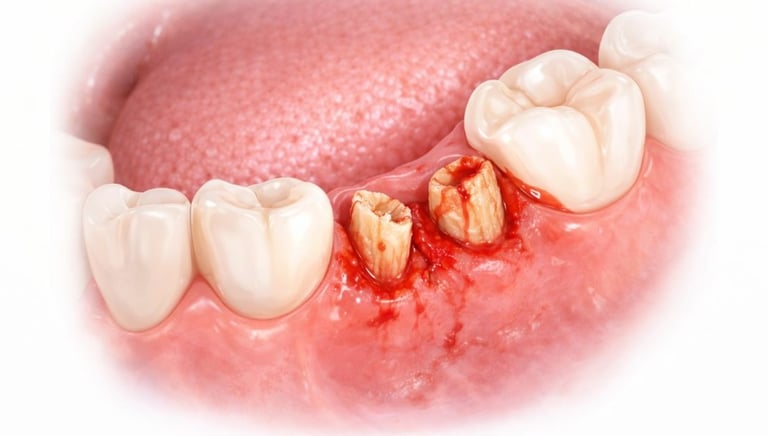

All images shown here represent real clinical cases of teeth extractions done at our dental clinic with patient consent.

Illustrative images and similar real clinical cases requiring tooth extraction